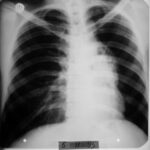

1991 Eylül - İlk Başvuru

Nefes darlığı, göğüs ağrısı - plevral sıvı

Teşhis

Az diferansiye fibröz malign mezotelioma

Ödem kayboldu, radyoloji normale yakın

Tetkiklerde sol plevra boşluğunda sıvı saptandı.

Torakoskopi ve Coparvacs uygulamasına rağmen akciğerde tam ekspansiyon sağlanamadı.

Radyolojik bulgular normale yakın hale gelmişti ve immünomodülatör tedaviyi kesmesi önerildi.